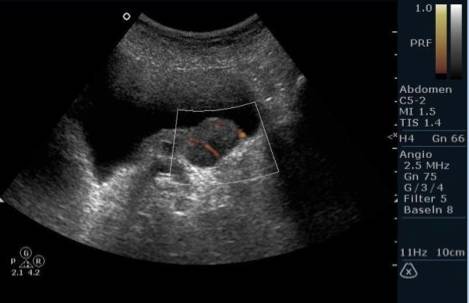

Диагностика

Обнаружить тяжи в амниотической жидкости можно с помощью ультразвукового исследования, которое проводится в начале второго триместра, хотя это не всегда удается. Нити могут быть настолько тонкими, что их сложно заметить на экране. Если у ребенка впоследствии будут выявлены деформации частей тела, то устанавливается соответствующий диагноз.

Если потребуется провести дополнительные исследования, то может быть назначено 3D-УЗИ, МРТ и эхокардиография плода. Эти процедуры необходимы для предотвращения серьезных последствий для здоровья малыша.

Амниотический тяж может быть диагностирован с помощью ультразвукового исследования. Врач может заметить аномальные структуры или волокна, которые могут указывать на наличие амниотического тяжа. Регулярные ультразвуковые обследования помогают отслеживать состояние плода и выявлять возможные осложнения на ранних стадиях.